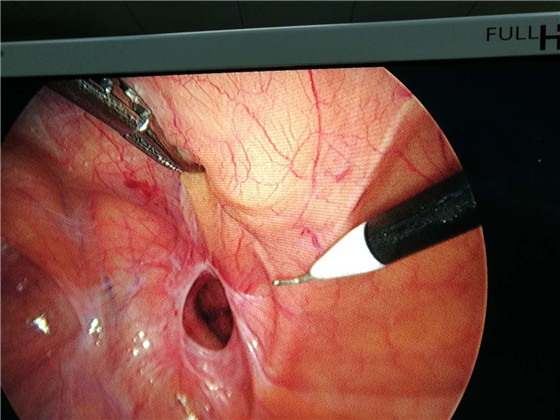

近日,我院普外科成功开展首例腹腔镜下腹股沟疝修补术。患者术后恢复良好,目前已治愈出院。此项手术的顺利开展不仅拓宽了我院腹腔镜的运用范围,也标志着我院微创外科水平又有了新的突破。

腹股沟疝是外科的常见病、多发病,手术是治疗成人腹股沟疝唯一有效的方法。与传统的腹股沟无张力疝修补术相比,微创的腹腔镜手术,创伤小,疼痛轻,恢复快,术后次日就可以进行日常生活,3-5天左右即可出院。为开展此项技术,我院选派了蒋结志和吴成成主治医师分别前往安徽省立医院和浙江邵逸夫医院进修学习微创外科手术。此次手术,在高有龙主任指导下,蒋结志主治医师和吴成成主治医师通力合作,成功完成了我院首例腹腔镜疝无张力修补术。